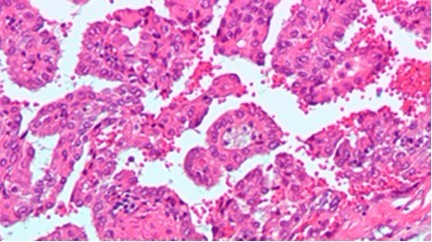

肾脏肿瘤,图片来自维基共享资源。

Swanton和他的同事们追踪肿瘤基因组进化并研究人肾脏肿瘤的遗传异常性。研究人员在一个病人所患的原发性肾脏肿瘤的几个位点及其几个转移瘤中进行活组织检测,并发现鉴定出的突变当中只有34%在病人所有样品中都是一样的。随后,他们构建出一个原发性肿瘤和一个转移瘤的进化树,结果表明一个癌细胞系在病人身上产生转移瘤,而另一个主要的癌细胞系支持原发性肿瘤生长,这些暗示着基于原发性肿瘤的活组织检测结果进行针对性治疗可能并不能有效地治疗转移瘤。Swanto说,如果能够发现哪些突变在肿瘤内不同细胞之间以及在不同肿瘤之间是相同的,那么科学家可能能够设计出一个更加全面的治疗策略。(生物谷:towersimper编译)